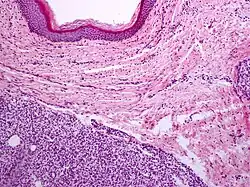

A precise history of the growth characteristics of the IH can be very helpful in making the diagnosis. In the first 4 to 8 weeks of life, IHs grow rapidly with primarily volumetric rather than radial growth. This is usually followed by a period of slower growth that can last 6–9 months, with 80% of the growth completed by 3 months. Finally, IHs involute over a period of years.[36] The exceptions to these growth characteristics include minimally proliferative His, which do not substantially proliferate[35] and large, deep IHs in which noticeable growth starts later and lasts longer.[36] If the diagnosis is not clear based on physical examination and growth history (most often in deep hemangiomas with little cutaneous involvement), then either imaging or histopathology can help confirm the diagnosis.[33][37] On Doppler ultrasound, an IH in the proliferative phase appears as a high-flow, soft-tissue mass usually without direct arteriovenous shunting. On MRI, IHs show a well-circumscribed lesion with intermediate and increased signal intensity on T1- and T2-weighted sequences, respectively, and strong enhancement after gadolinium injections, with fast-flow vessels.[33] Tissue for diagnosis can be obtained via fine-needle aspiration, skin biopsy, or excisional biopsy.[38] Under the microscope, IHs are unencapsulated aggregates of closely packed, thin-walled capillaries, usually with endothelial lining. Blood-filled vessels are separated by scant connective tissue. Their lumina may be thrombosed and organized. Hemosiderin pigment deposition due to vessel rupture may be observed.[39] The GLUT-1 histochemical marker can be helpful in distinguishing IHs from other items on the differential diagnosis, such as vascular malformations.[34]